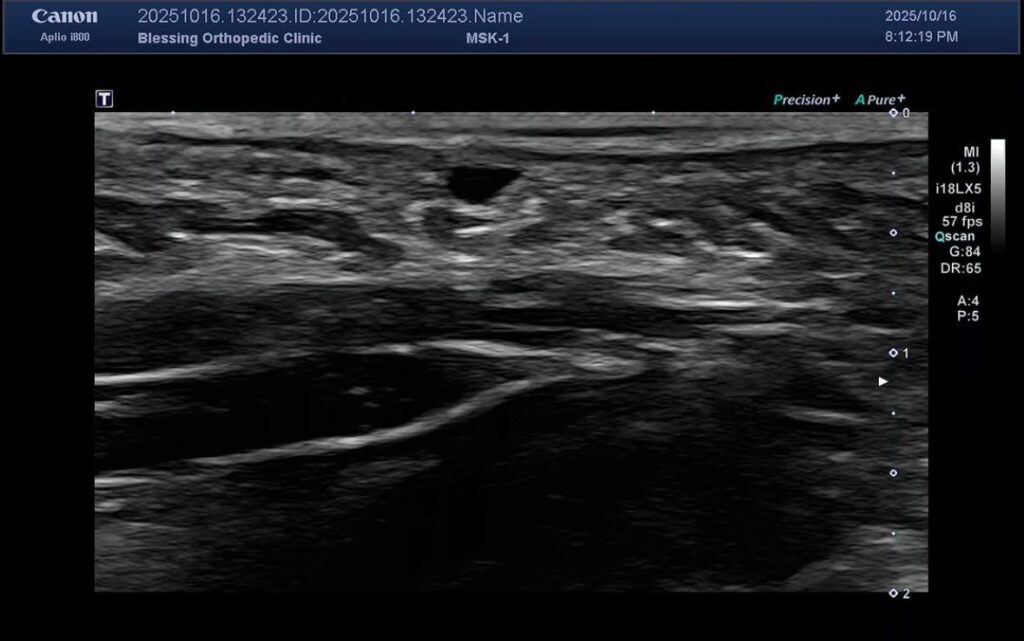

長期勞動者主訴手掌有個點壓了就會有被電擊的麻感,超音波看到腱鞘囊腫(Ganglion cyst)正好在指神經(Digital nerve)上,一壓迫就會刺激到神經,長期勞動更有可能讓關節囊出現小受損導致關節液洩漏,如果受損的孔洞成為單向閥門,讓關節液只出不回,就可能產生腱鞘囊腫,當腱鞘囊腫引起不適或壓迫到神經時,可以考慮以下幾種處理方式:輕微的可以先觀察、改變活動習慣或穿戴護具。

若症狀持續,可以考慮用針將囊腫內的關節液抽出,有時會合併注射少量類固醇以減少復發。對於反覆發作或症狀嚴重的案例,也可以考慮用手術方式將囊腫連同其根部來源的關節囊一併切除。不過,具體適合哪種方式,仍需由醫師專業評估紅圈處低回音(黑色)結構是「腱鞘囊腫」,在他下面的蜂巢狀結構是「指神經(Digital nerve)」